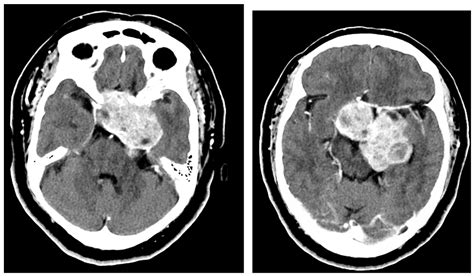

MRI (Magnetic Resonance Imaging) Provides high-resolution images of soft tissues, nerves, and the brain.

CT Scan (Computed Tomography) Highly effective at highlighting bony structures and identifying tumor-related bone erosion.